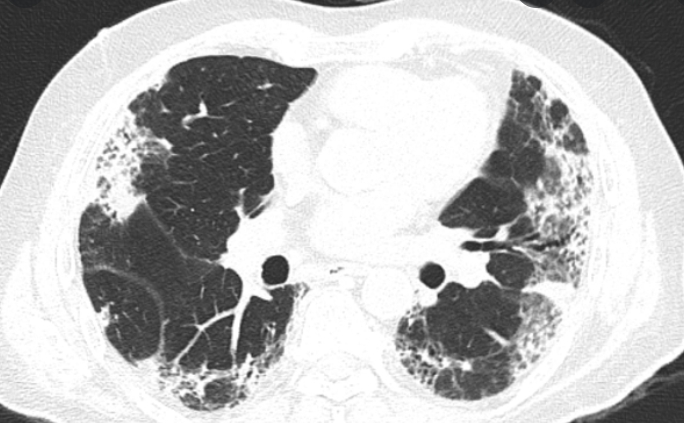

Hình ảnh Xơ phổi ở bệnh nhân Hậu Covid

Các rối loạn về cơ quan hô hấp là một trong các di chứng thường gặp và nguy hiểm nhất của người bệnh sau khi nhiễm COVID-19. Theo Hiệp hội Bệnh phổi kẽ vương quốc Anh, phân tích gộp các nghiên cứu quan sát ban đầu đã xác định được một tỉ lệ đáng kể bệnh nhân có bệnh phổi kẽ liên quan đến COVID kéo dài với ước tính 27% bệnh nhân được chụp cắt lớp vi tính ngực có dấu xơ phổi trong thời gian nhập viện điều trị COVID và ước tính 33% có xuất hiện tình trạng xơ phổi sau 6 tháng, điều này cho thấy sự tiến triển xơ hóa phổi theo thời gian. Tương tự, khi khảo sát các đối tượng hậu COVID từ 01 đến 06 tháng, kết quả cho thấy ước tính có 45% bệnh nhân có suy giảm chức năng thông khí, 21% bệnh nhân có rối loạn chức năng hô hấp hạn chế.